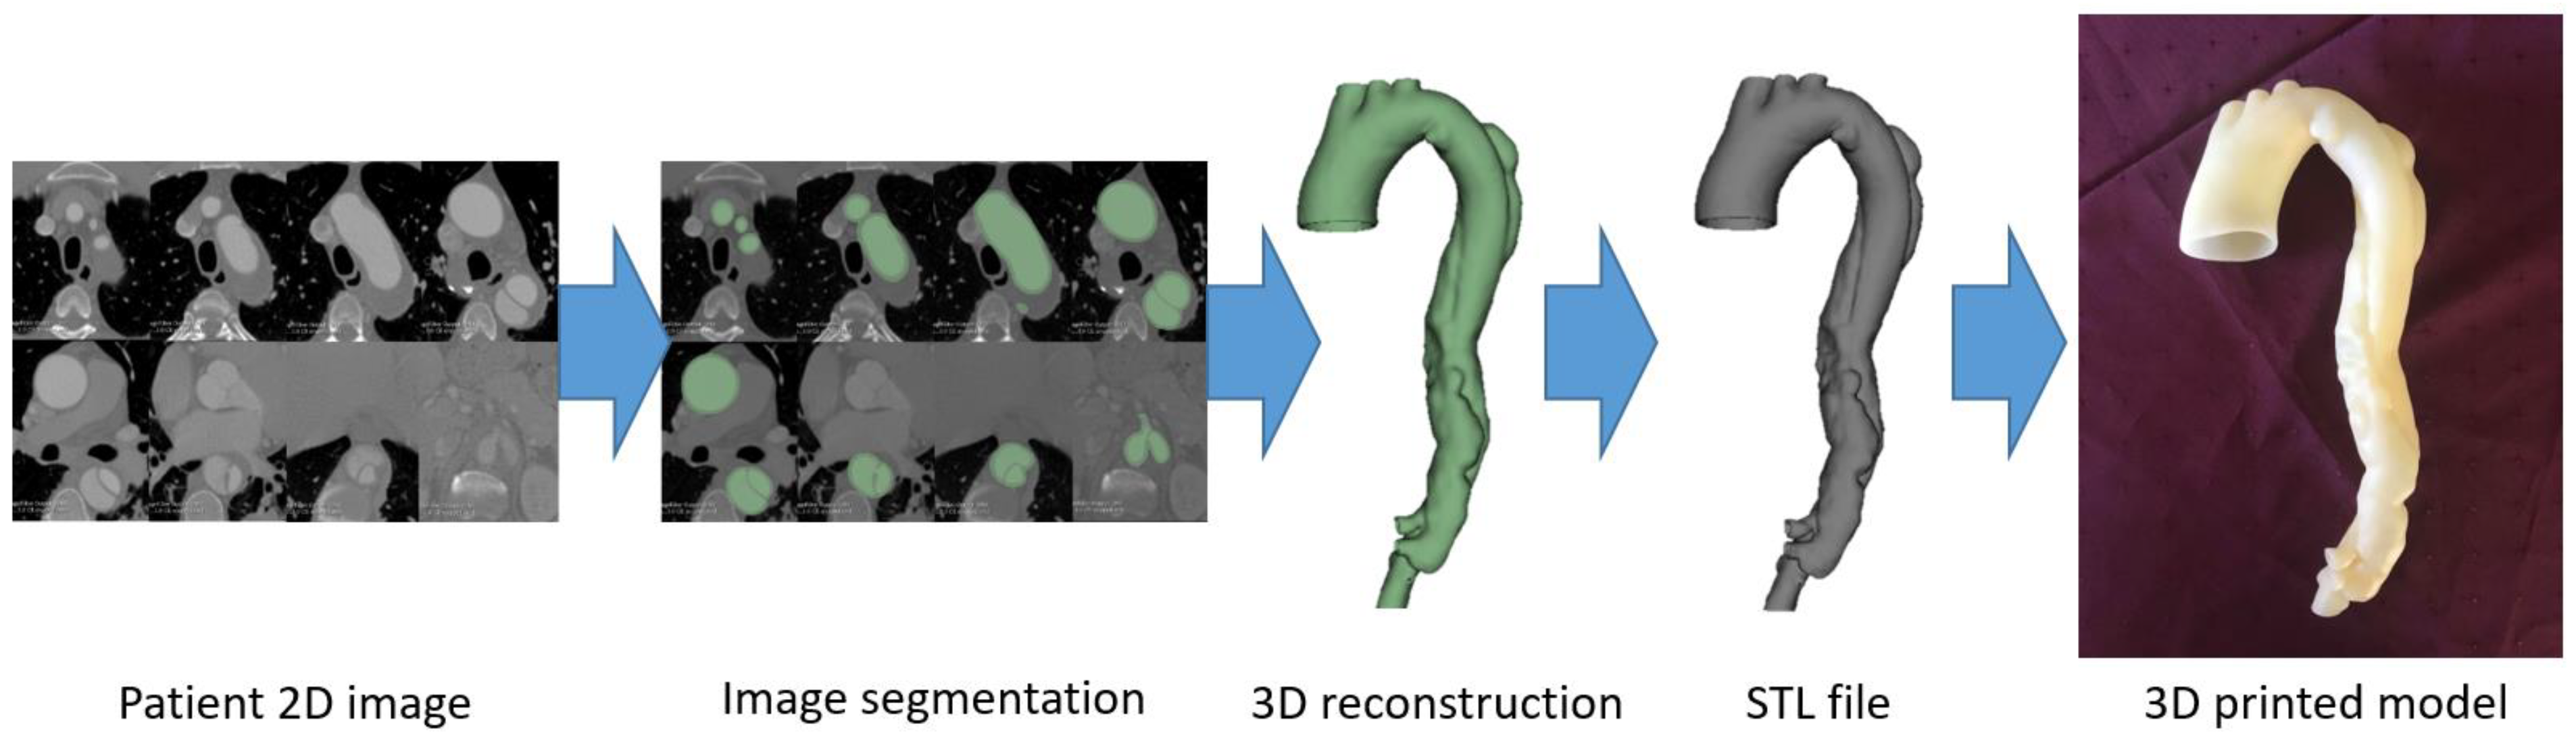

2. 3D Printing Preparation: Image Post-Processing and Segmentation